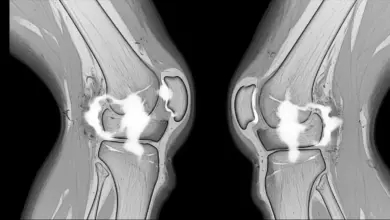

A ressonância magnética pode ajudar, principalmente quando há dúvida diagnóstica ou necessidade de afastar outras lesões associadas.

Ainda assim, o exame precisa ser interpretado junto com a avaliação clínica. Nem toda plica visível no exame é a verdadeira causa da dor.